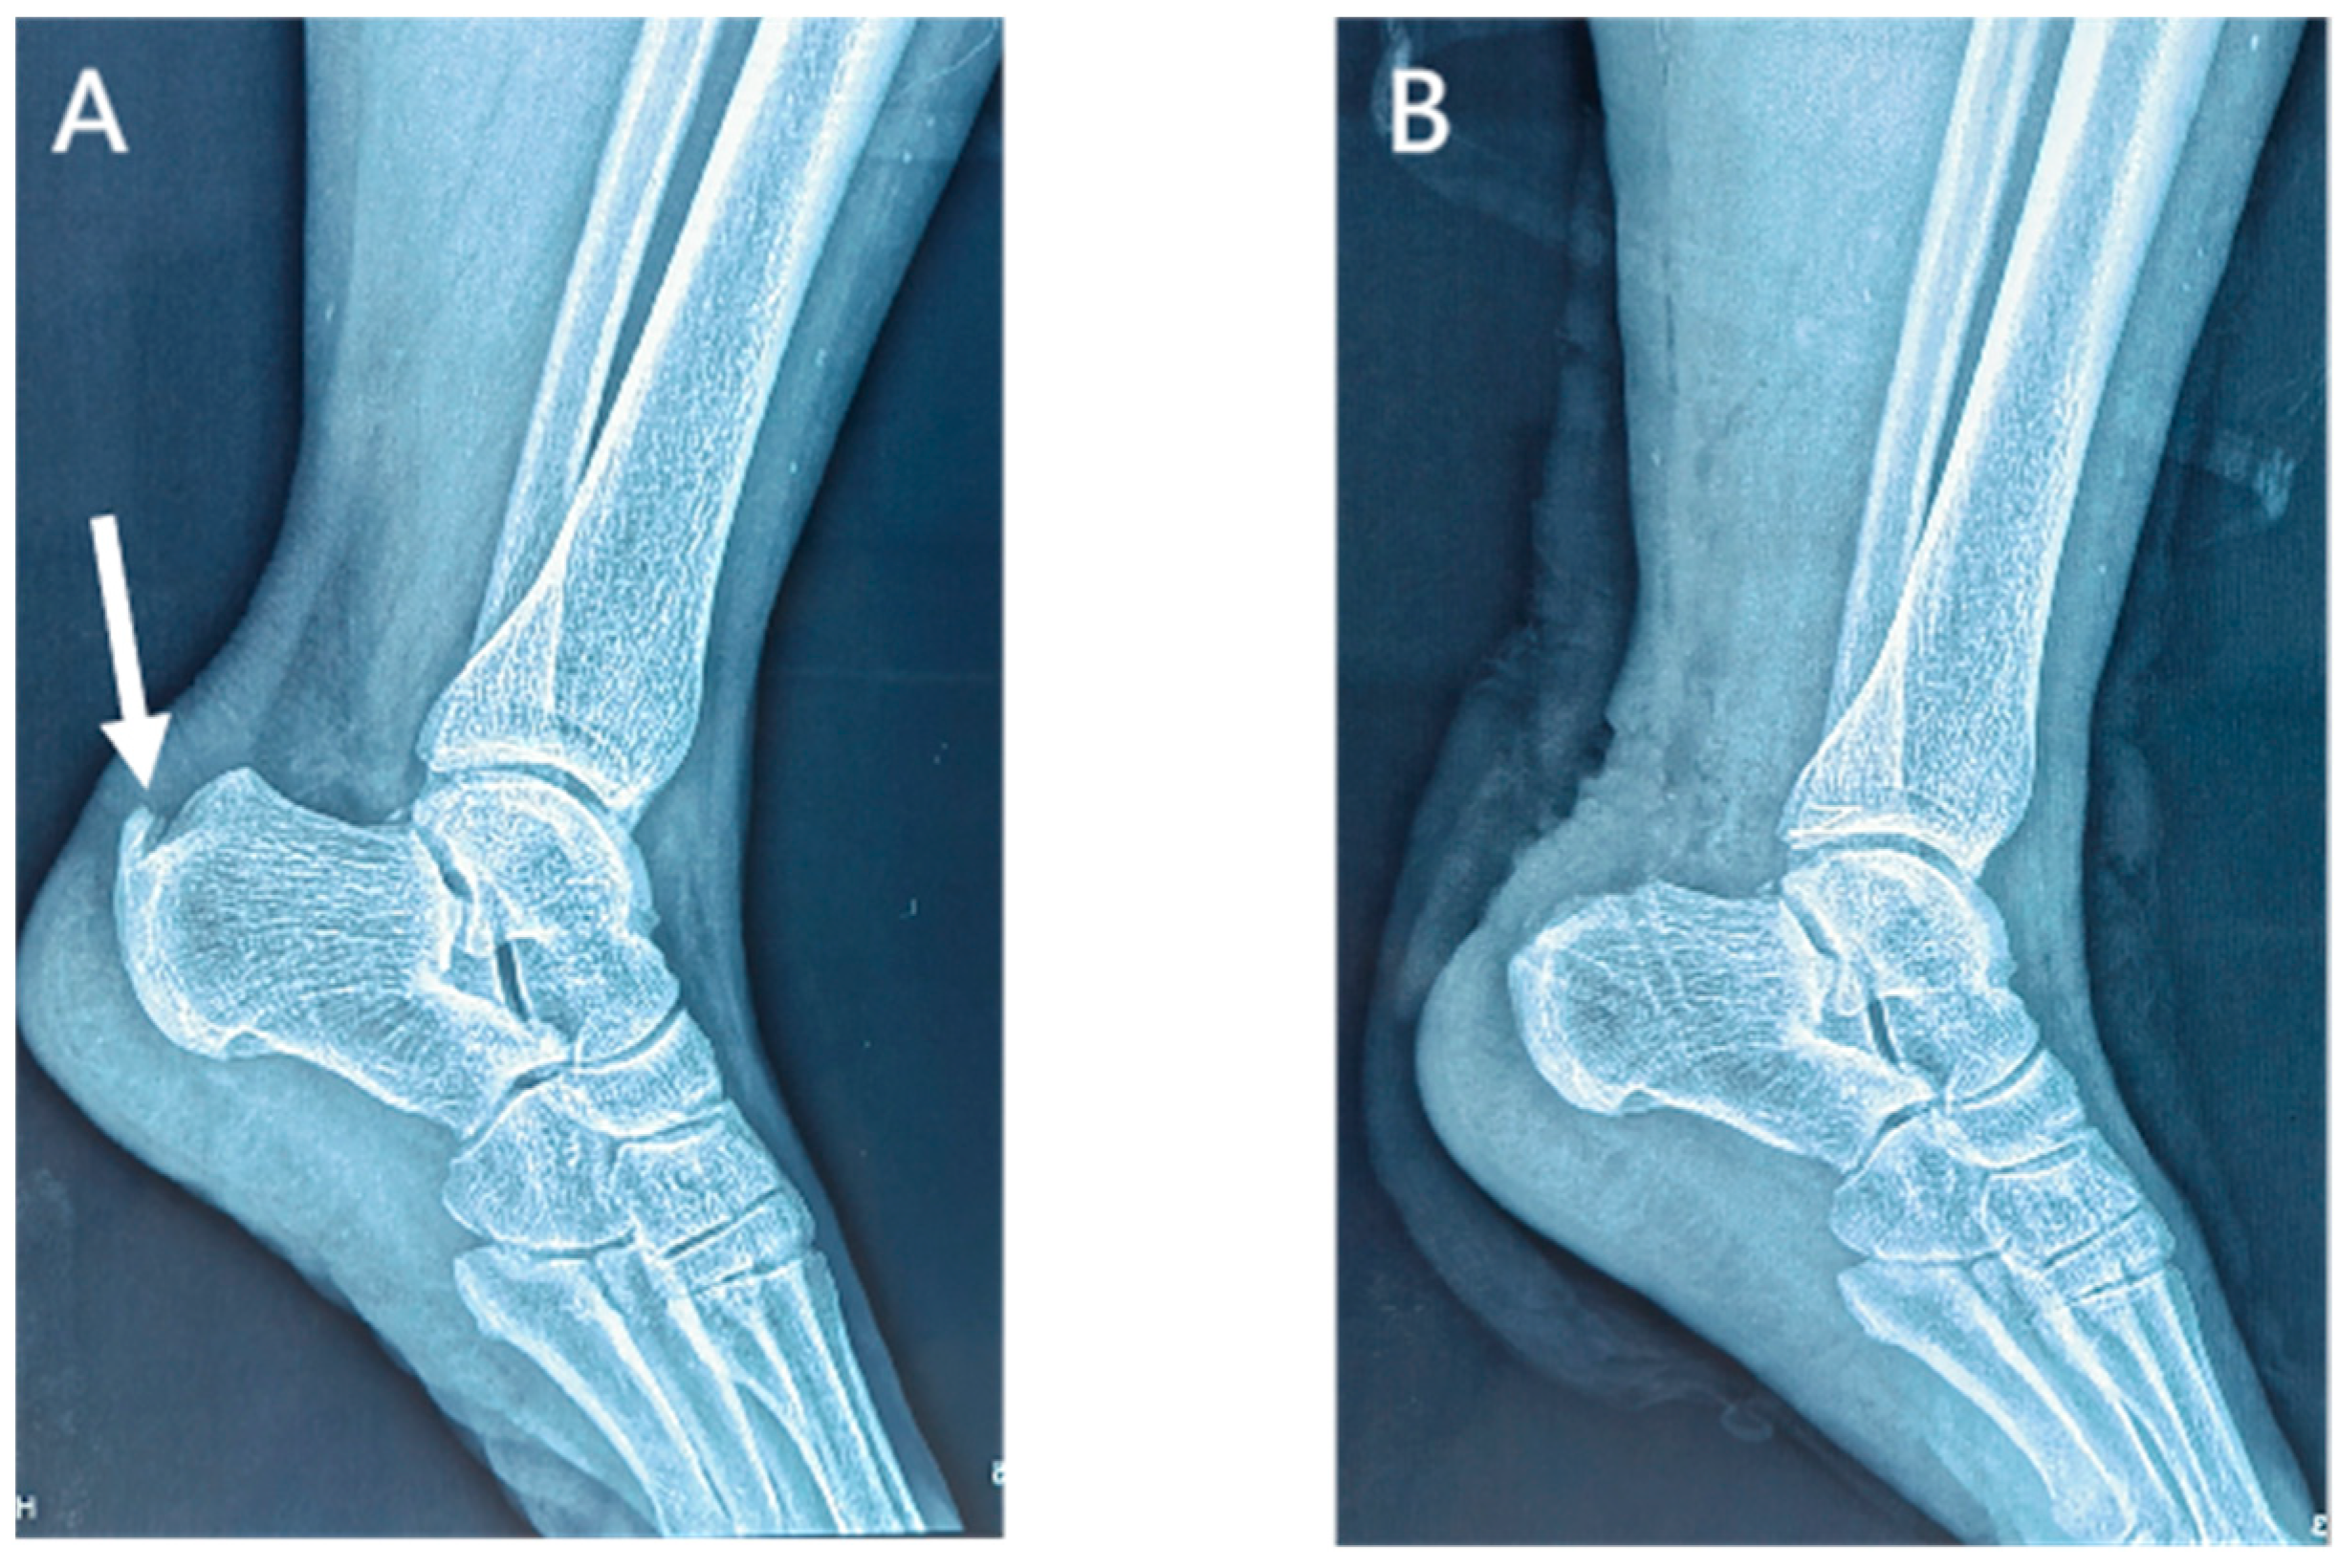

Lateral radiographs of the ankle 1 day postoperatively showed the complete removal of the calcific lesions in the Achilles tendon (Figure 3 and Figure 4). No loosening or fracture of the anchors occurred during the follow-up. All the surgical wounds healed well with no infection, scar, or dehiscence. No severe complications occurred, such as sural nerve injury, saphenous vein injury, or venous thrombosis. No patients experienced Achilles tendon rupture, contracture, or adhesion. There was no significant difference in the range of motion between the affected ankles and the contralateral ones (dorsiflexion: 23.7 ± 1.5 vs. 23.8 ± 1.9 degrees, p = 0.503; plantar flexion: 38.8 ± 2.2 vs. 39.3 ± 2.1, p = 0.080). At the last appointment, all 25 patients were asymptomatic and had returned to their pre-injury levels of activity and mild sports.

Figure 4.

Preoperative (A) and postoperative (B) lateral radiographs of the ankle in the suture bridge group. Arrow, a calcific lesion in the Achilles tendon.